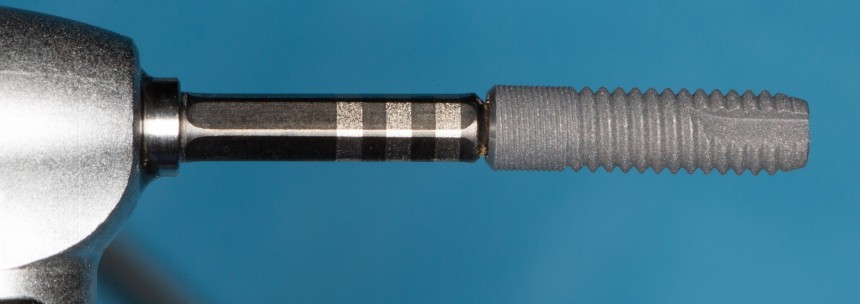

В связи с этим, мы выбираем имплант Dentsply Astratech диаметром 3.5 и длиной 13 мм. Это — минимальный диаметр импланта, на котором возможно эстетическое протезирование. Под данный размер платформы есть полный набор супраструктур — и это облегчает работу ортопеду.

Устанавливаем имплантат в лунку зуба:

Обратите внимание на глубину погружения импланта и расстояние от его стенки до корня зуба. Не нужно пытаться добиться высокой первичной стабильности путем чрезмерного погружения импланта. Это создаст сложности при протезировании. Лучше выставить его в правильное положение с оглядкой на соседние зубы (шейка импланта на уровне шеек естественных зубов), забыть про первичную стабильность (не так важна, как кажется) и недостаток окружающих тканей. Последние можно восстановить остеопластическими методами.